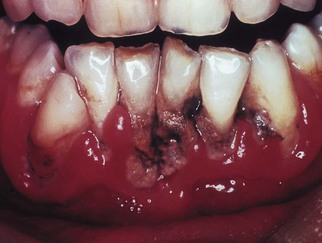

Clinical features

The condition is characterized by actually inflamed, red, shiny and bleeding gingivae with irregularly shaped ulcers, which initially appear on the tips of the interdental papillae. If untreated, the ulcers enlarge and spread to involve the marginal and, rarely, the attached gingivae (Fig. 33.6). The lesions are extremely painful and are covered by a pseudomembrane (or slough), which can be wiped from the surface. The slough consists of leukocytes, erythrocytes, fibrin, necrotic tissue debris and microorganisms. Characteristically, the patient’s breath is malodorous. The patient may complain of an unpleasant metallic taste. There is little or no systemic upset, and mild submandibular lymphadenitis; involvement of the cervical lymph nodes only occurs in severe cases. Generalized fever or malaise is very uncommon.

image

Fig. 33.6 Acute necrotizing ulcerative gingivitis. Note the loss of papillae, spontaneous bleeding and gross plaque accumulation.